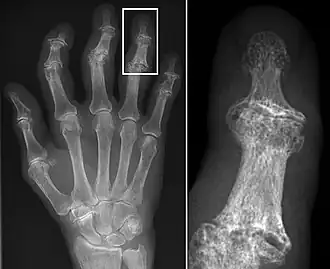

Osteoarthritis (OA) is a degenerative joint disease that affects the junctions of articulating elements, or synovial joints (e.g. knee, shoulder) and is characterized by the damage of cartilage. OA is the most commonly documented pathology found in archaeological human remains and has been used extensively as an activity marker that reflects stress-related activity patterns or occupation.[11] Factors such as age, sex, body size and others also affect its expression.[12]

Kathryn Marklein from the Ohio State University explored the prevalence of OA between two Roman period (2nd – 3rd c. CE) skeletal assemblages retrieved from mass graves in Oymaağaç, Vezirköprü, Turkey. It was previously indicated through the analyses of non-metric traits that several individuals from one of the mass graves demonstrated biological relatedness with each other. In order to establish an approach for the evaluation of a possible genetic and socio-historical context correlated with OA, Marklein’s aim was to test if comparing different OA distribution patterns between familial and non-familial groups can indicate familial relatedness at Oymaağaç. Ten synovial joints were selected for the study among adults from site 1 (17 individuals) and site 2 (23 individuals). The study found no significant data to suggest a correlation between OA and different burial group, nor a correlation between OA and biologically related individuals.[13]